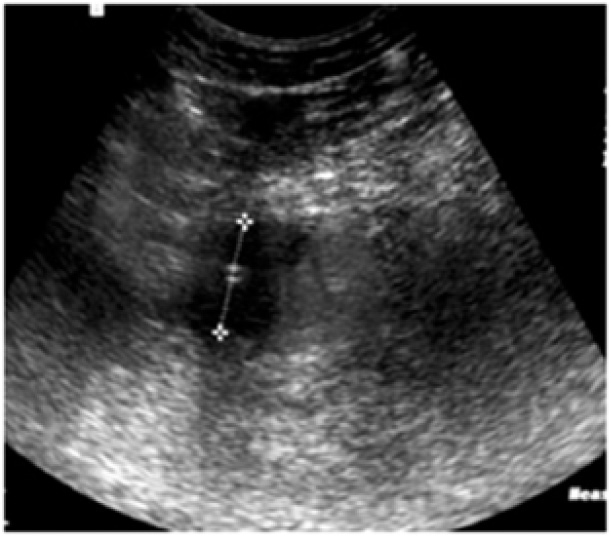

Учитывая наличие недренирумых отграниченных жидкостных скоплений, выполнено пункционное дренирование под ультрасонографическим контролем на 23-е сут после ГПДР (рис. 8).

Рис. 8. Ультрасонограмма. Отграниченное жидкостное скопление в области ПЕА